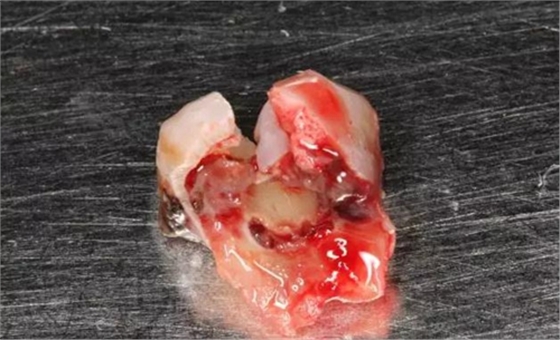

圖7. 37牙冠碎裂。多生牙壓迫吸收程度嚴重。

圖8.拔除的37頰側(cè)的牙根完全被壓迫吸收完。